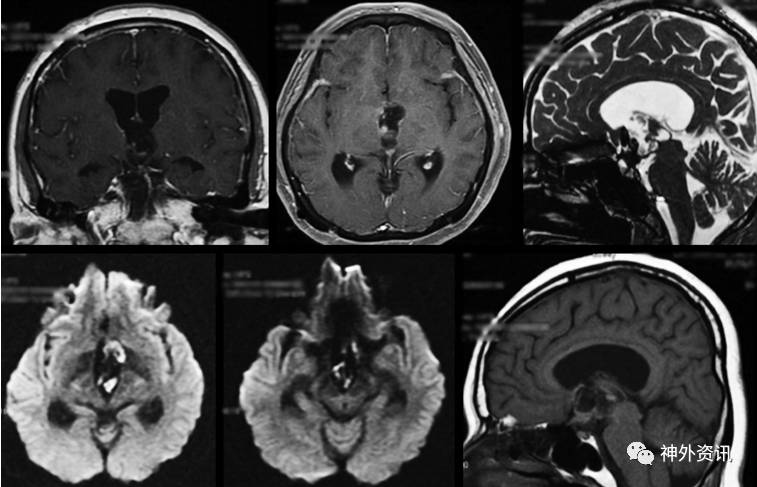

2年后,患者出现阵发嗜睡、定向障碍和精神淡漠等症状,持续时间从数小时至数天。已停经15年。神经系统检查发现嗜睡和定向障碍,伴视野缺损。内分泌检查显示激素水平正常。MRI成像提示三脑室内病变增大,T1加权为不均匀高、低信号,T2加权高信号(图2)。

图2. 第二次入院的颅脑MRI成像。